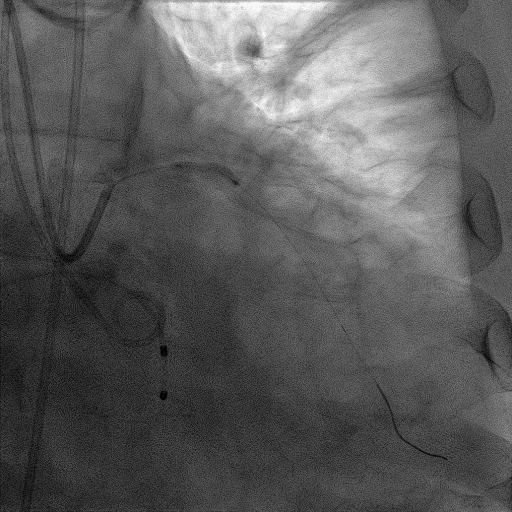

造影提示微少量返流,压力监测提示主动脉瓣压差7mmHg

手术过程

患者麻醉方式为全麻,建立静脉通路后,穿刺右侧股静脉,预埋ProGlide缝合器,食道超声指导下房间隔穿刺成功,将Superstiff导丝送至左房,应用18F鞘管扩张穿刺部位,沿导丝将导引导管送入左房,MitraClip调整后顺利到达二尖瓣目标位置,在X线及食道超声辅助下,将Mitraclip NTR成形夹精确定位后,成功夹合二尖瓣A2-P2区,超声显示反流明显减少,多切面证实夹合组织充分,肺静脉多普勒波形由反向恢复正常,手术顺利结束,安返普通病房。